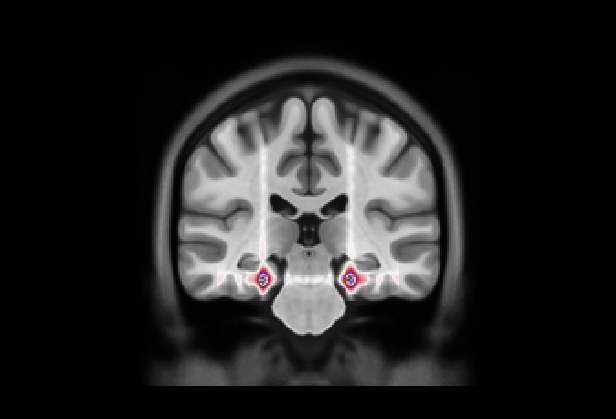

(a) Axial

Refer to caption

(b)

(c) Coronal

(d) Fold 1

(e) Sagittal

(f)

(g)

(h) Fold 2

(i)

(j)

(k) Fold 3

(l)

(m)

(n) Fold 4

(o)

(p)

(q) Fold 5

(r)

Figure 5: Average attention weight distributions generate by our model for each fold and each plane

Many studies focused on model interpretability by generating saliency maps for randomly chosen test subjects, enabling local qualitative analysis. However, this approach does not support the evaluation of interpretability consistency when the training and testing data vary. To examine this consistency in our approach, we considered the variability of attentional weight distributions across the five different folds used for cross-validation. Our evaluation leverages a clinical hypothesis specific to AD, which is believed to affect similar brain areas across different patients. For each fold, we calculated the weight distributions for each sample in the test set and derived an average distribution specific to that test set. By analyzing these average distributions across the five folds, we could assess whether our interpretability remained consistent, thereby supporting the generalizability of our findings across different subsets of data.

Fig. 5 presents our diagnosis network’s average attentional weight distributions for each fold in the axial, coronal, and sagittal views. Upon examination of the histograms for each view, we observe a remarkable consistency in the distribution shapes across all five folds, indicating that our interpretability approach is stable despite the variation in the train/test set data. Specifically, the axial distributions reveal a consistent concentration of attentional weights around the initial slices. This trend suggests the model’s recurrent focus on the brain’s inferior regions, notably the areas where degenerative changes first manifest in AD, such as the hippocampus. In the coronal view, attentional weights are notably centered, indicating that the model consistently identifies the central part of the brain as significant. This central focus might correspond to the medial temporal lobe, including the hippocampus and the surrounding regions, further substantiating the axial findings. The sagittal view is the only bimodal distribution, suggesting that the model pinpointed symmetrical areas along this plane. We hypothesize that the network was focusing on the hippocampus since it adheres to all the constraints: situated in the inferior part of the brain, centrally located, and symmetrical. The consistency and specificity of these findings across multiple data folds strengthen the argument that our network could reliably identify specific brain regions as a critical biomarker for distinguishing between AD and CN subjects.